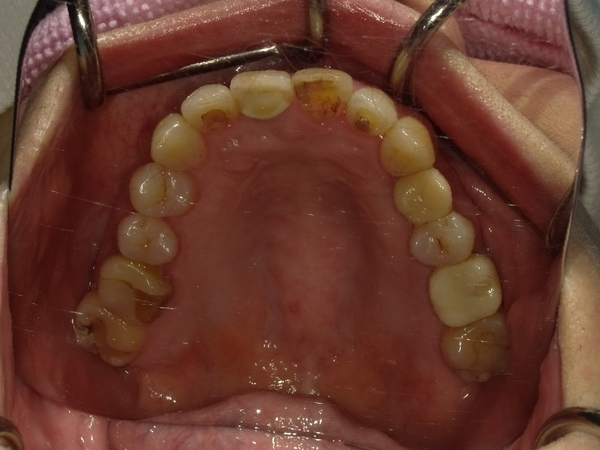

ガタガタとした歯並びや八重歯(叢生)CASE75